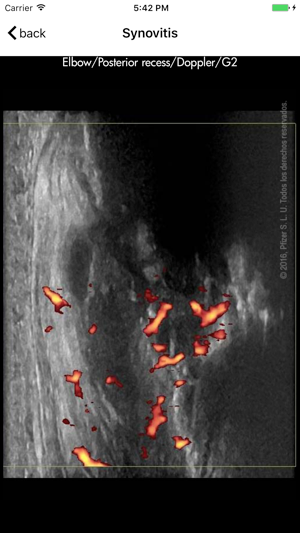

Ultrasound detected synovitis is a powerful imaging tool used worldwide that helps diagnose, monitor and treat patients with rheumatoid arthritis . RAUSSA application has been developed to help you score joint and tendon ultrasound grey scale and Doppler detected synovitis while performing your ultrasound examination. RAUSSA is made-up of almost 400 images from patients with rheumatoid arthritis. Takes no more than 2 minutes to learn! In every area you can look at a representative anatomic specimen image, up to 4 different US images with the same grey scale or Doppler mode score. , Dr. J. Uson MD PhD , Dr. I. Möller MD PhD and Dr. E. Naredo MD PhD, experts in rheumatologic ultrasound have obtained the images in this app.

The ultrasound definitions and semi-quantitative scoring method used in this app. are those driven and reported by OMERACT (Outcome Measures in Rheumatology in Clinical Trials) validated for diagnoses and monitoring inflammatory activity in patients with rheumatoid arthritis (Bruyn GA, Naredo E, Iagnocco A. J Rheumatol 2015;42 (11):2172-6).